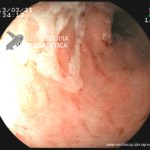

- Doença de Crohn em atividade leve